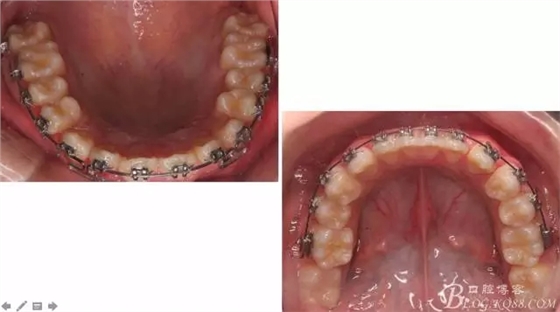

佩戴三個月的FR2, 效果奇佳!前牙基本達到淺覆蓋,淺覆合!接下來進入二期直絲弓固定正畸,排齊階段!

一晃快兩年了,我覺得關節(jié)重建及咬合穩(wěn)定,再加上患者的急迫愿望,我們拆除了矯正器。

尖牙關系中性,磨牙關系中性,咬合鎖結良好!